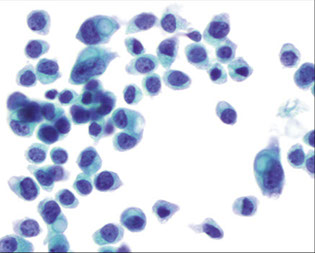

Medullary Carcinoma

Seen more often in younger women (10% younger than 35 years of age).

- Presents as a soft round mobile mass that can be mistaken clinically for fibroadenoma.

FNA shows a cellular specimen composed of large pleomorphic malignant cells arranged singly and in loose syncytial aggregates

Lymphocytes and plasma cells are numerous in the background

The nuclei are enlarged and pleomorphic with irregular nuclear contours, abnormal chromatin distribution and prominent to macro nucleoli

The cytoplasm is fragile, delicate and lacy with indistinct cell borders.

Occasional naked nuclei can be seen in the background (not to be confused with myoepithelial nuclei)